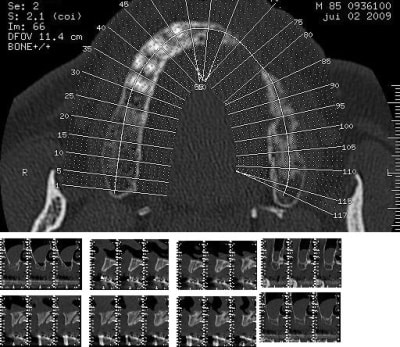

15/07/2009 à 23h52

> le pano bof...

C'est quoi ton plan de traitement ????

16/07/2009 à 01h14

>

rehabilitation max sup et inf

transvissée au max (amovo inamovible) refection 4 ccm restantes

prothese fixée à la mdble ccm sur 43

bruxisme prononcé

85 ans en pleine forme mais je fais en plusieurs fois pour ne pas trop le fatiguer.

Merci pour cette expérience partagée. Belles photos. Merci aussi d'avoir l'honnêteté de présenter un cas qui ,s'il paraît franchement parfait sur les photos de chir, l'est un poil moins sur la pano (mais c'est qu'une pano). De toute façon avec une expérience comme la tienne la gestion prothétique se fera sans doute sans trop de soucis.

pour la prothèse, je ne me fais pas de souci mais la pose sur le pano me plait tres moyennement, alors qu'en bouche ça paraissait axé comme il faut.